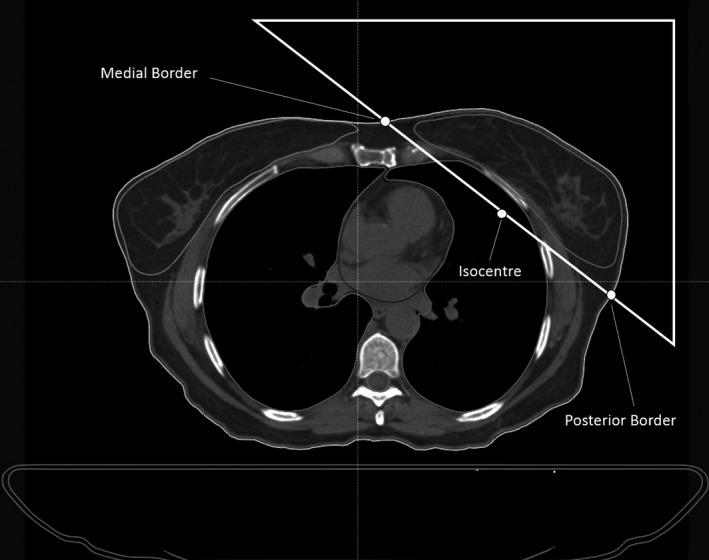

To present the development of an in-house coded solution for treatment planning of tangential breast radiotherapy that creates single click plans by emulating the iterative optimization process of human dosimetrists.

One hundred clinical breast cancer patients were retrospectively planned with an automated planning (AP) code incorporating the hybrid intensity-modulated radiotherapy (IMRT) approach. The code automates all planning processes including plan generation, beam generation, gantry and collimator angle determination, open segments and dynamic IMRT fluence and calculations. Thirty-nine dose volume histogram (DVH) metrics taken from three international recommendations were compared between the automated and clinical plans (CP), along with median interquartile analysis of the DVH distributions. Total planning time and delivery QA were also compared between the plan sets.